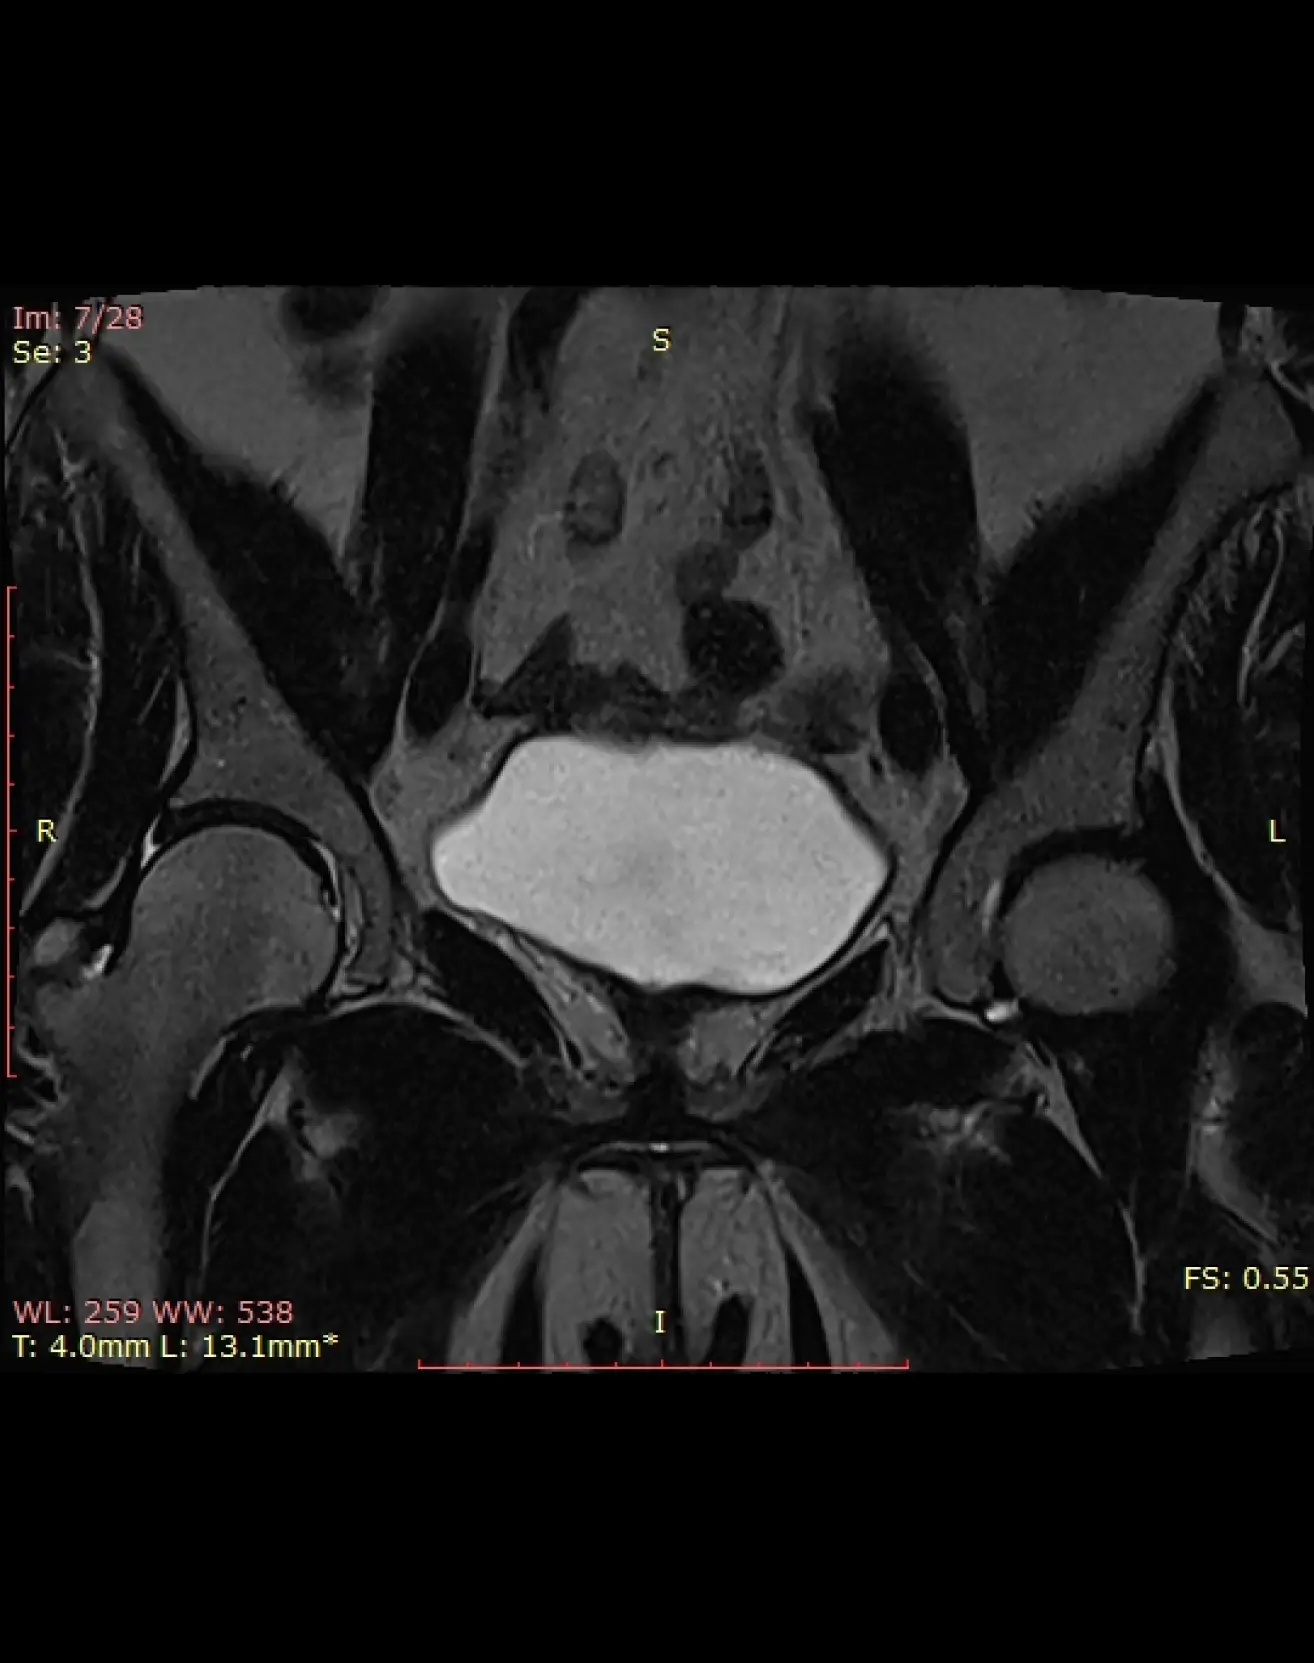

МРТ малого таза у женщин

Визуализация матки, яичников, маточных труб, влагалища, лимфоузлов, параметральных вен, прямой кишки.